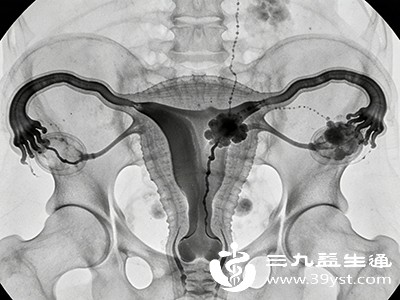

在女性生殖系统相关检查中,输卵管造影检查是评估输卵管通畅程度的重要手段,对于备孕困难或怀疑输卵管存在问题的女性而言,这项检查意义重大。然而,由于对检查流程不了解,不少人会感到紧张和担忧。其实,只要熟悉输卵管造影检查的各个环节,就能更好地配合医生,顺利完成检查。接下来,将从检查前准备、检查过程以及检查后的注意事项等方面,详细介绍输卵管造影检查的具体做法。

二、检查过程详解